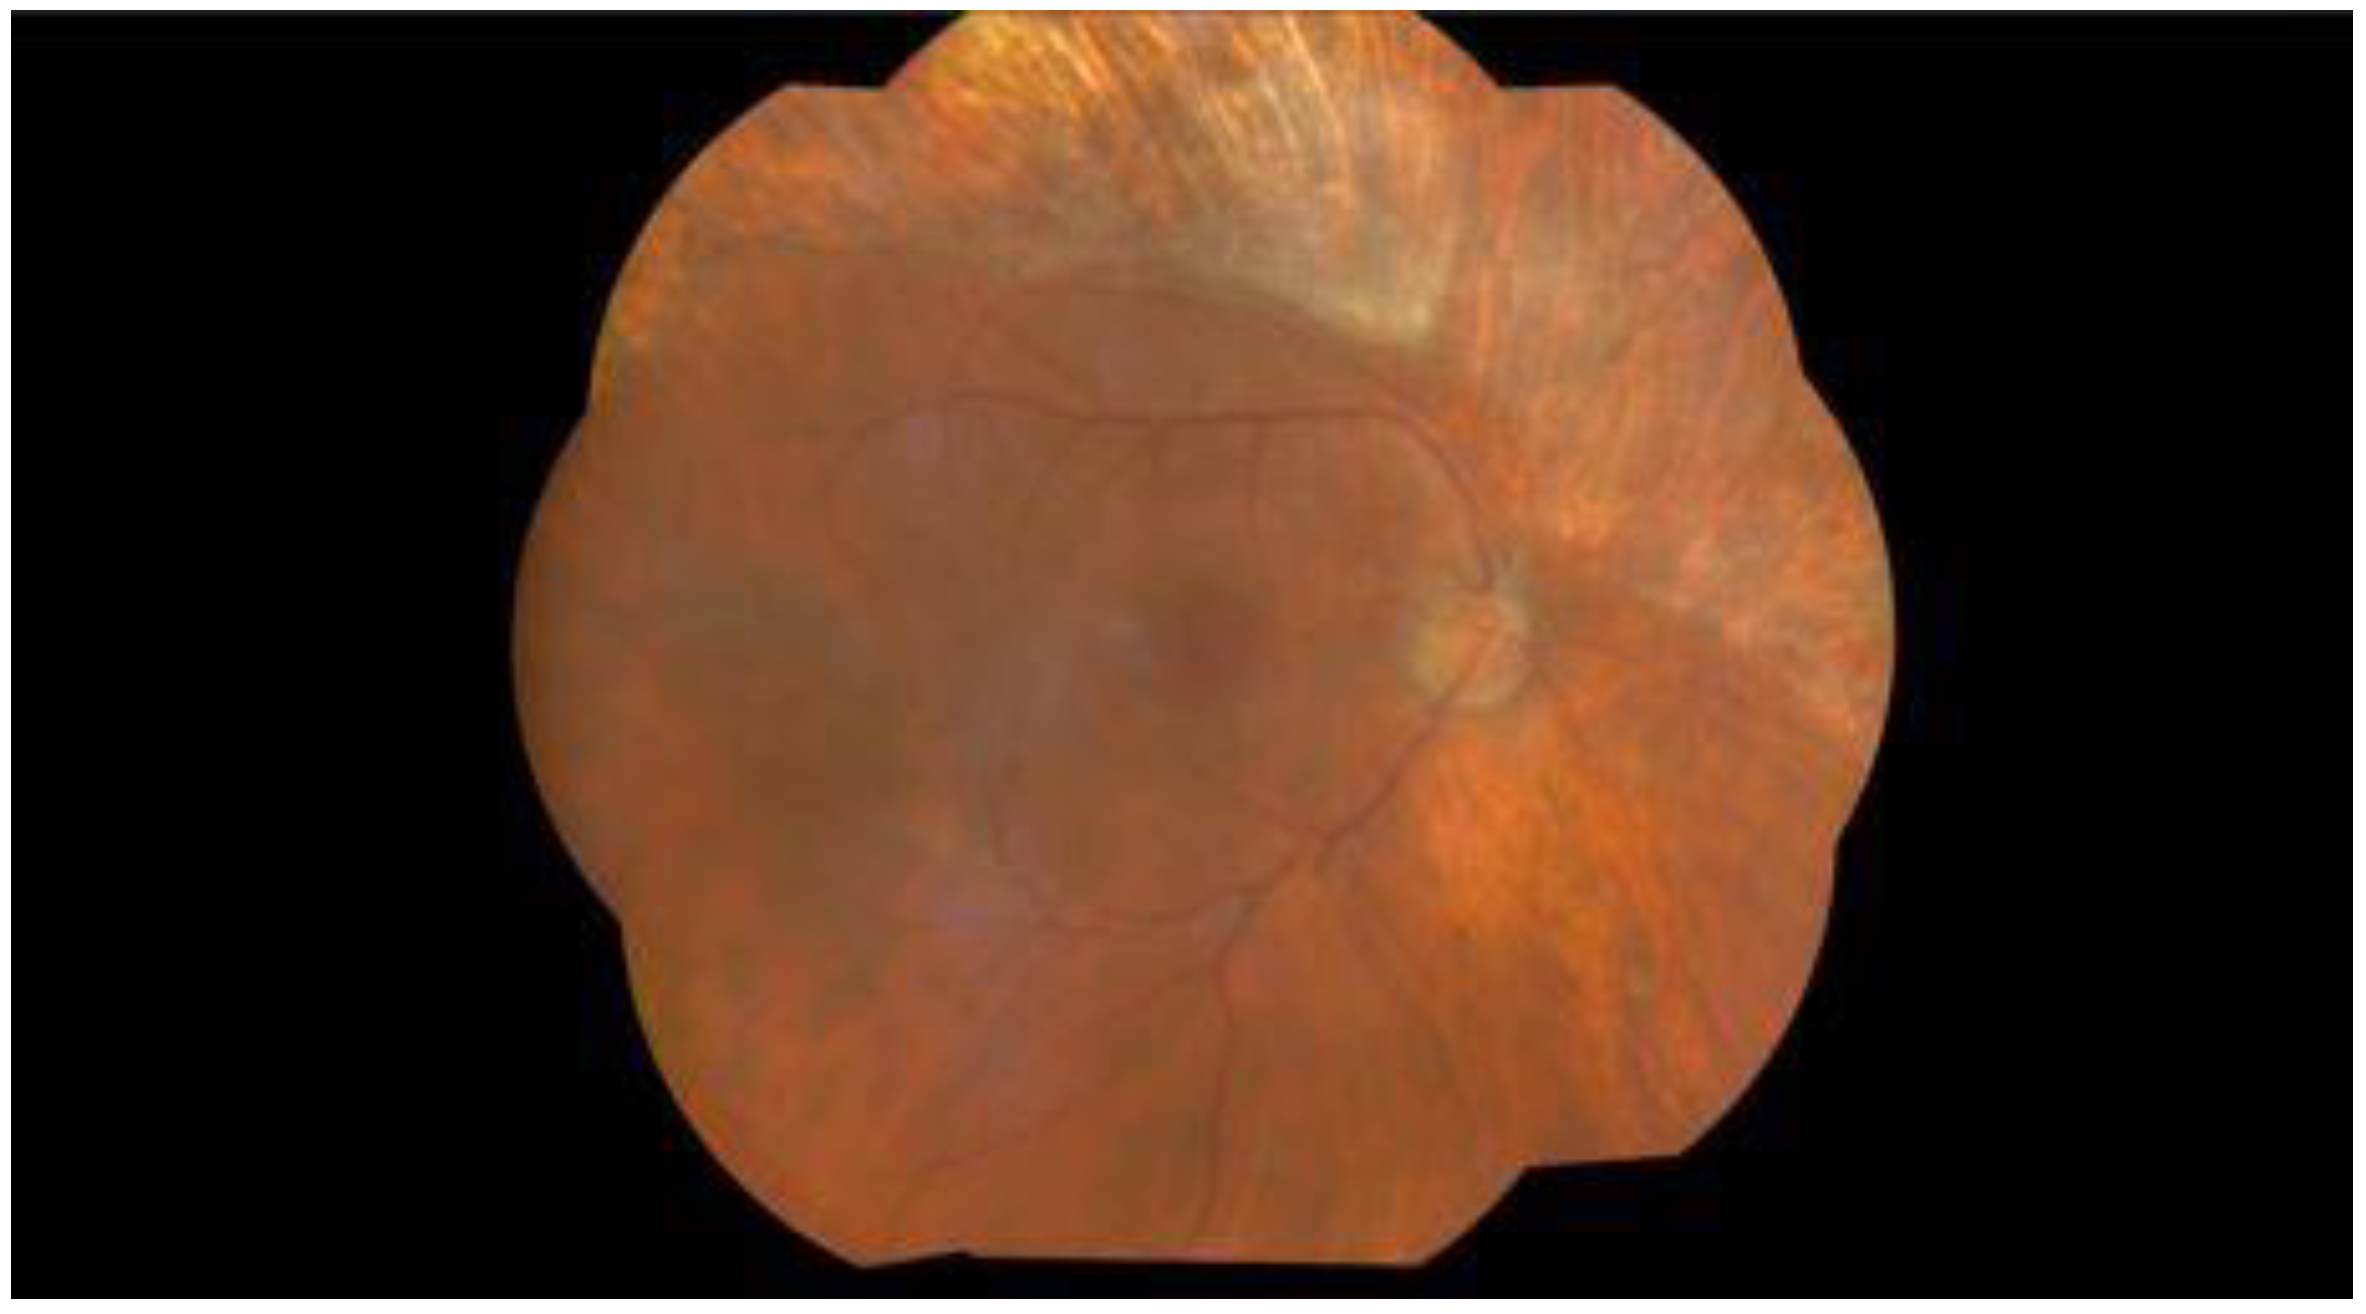

Maintenance therapy with 900 milligram (mg) tablets of valganciclovir was continued for 4 months, when fundus examination showed scarring at the site of the previous retinitis in the left eye but no improvement in the visual status (Figure 4 and Figure 5). CMV retinitis has also led to a very serious complication of retinal detachment in his left eye. His follow-up during the next months showed no recurrence of CMV retinitis lesions or evidence of any disseminated CMV disease.

Figure 4.

Wide-field fundus photographs of the right eye. Four months after the first presentation, the right eye shows no signs of CMV reactivation or complications.